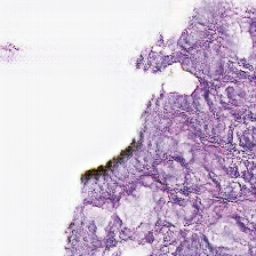

For Target Domain, the MHIST dataset [2] is used (available at https://bmirds.github.io/MHIST/ ), which contains high quality H&E stained histopathology images suitable for learning realistic color and texture distributions.Jana The dataset contains 3,152 H&E images. Some examples are displayed in Figure 1.

The Figure 3 shows virtual H&E generation from light-sheet microscopy image. Each column represents a different type of image. Each row corresponds to a different slice. From these images, it can be observed that the CycleGAN has learned to map the nuclear and cytoplasmic signals to the characteristic H&E colors. Overall tissue morphology and structure are largely preserved, demonstrating that the model captures the spatial relationships of nuclei and cytoplasm from the fluorescence channels.

| C01 | C02 | virtual H&E images |

|---|---|---|